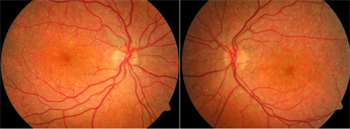

An 8-year-old female was referred for a choroidal lesion within the macula in the right eye with recent concern for enlargement. The patient had no vision symptoms in either eye and was systemically healthy. She was taking no medications. The family reported a healthy, full-term birth with no congenital or developmental anomalies.

Best-corrected visual acuity was 20/25 in both eyes. Intraocular pressure, pupil response, and anterior segment examination was normal in both eyes. Posterior segment examination of the left eye was normal. Within the macula of the right eye, there was a circular, well-circumscribed, yellow-orange subretinal lesion centered at the fovea. There was no vitreous cell or haze and the optic nerve and the remainder of the peripheral retina appeared normal.

| Lead Image: Color fundus photograph of the right eye showed a well-circumscribed, hypopigmented, macular lesion with foveal pigmentary changes. |